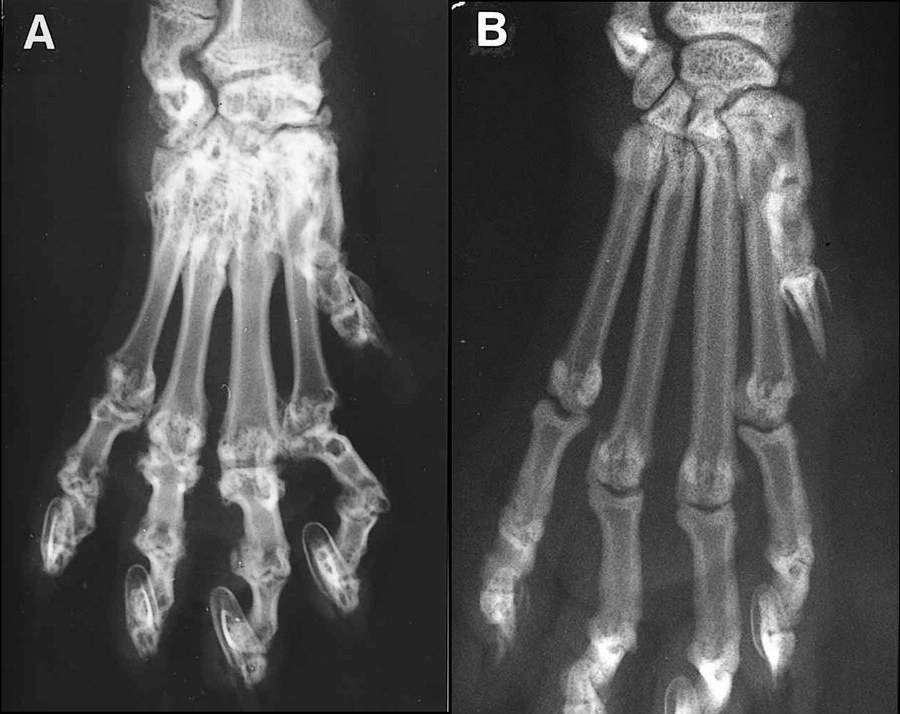

A图是发病的苏格兰折耳猫前肢的X光片,与B图中正常猫的前肢对比一下,就知道病猫受了多大的罪。

9 O. z+ s2 N) R! X  A5 a在出生几个月到几年后,这只可怜的FdFd猫的四个爪子和尾巴的骨骼就会发生畸形。这样的猫,走起来路会一瘸一拐,动作也格外僵直,尾巴则会变得又粗又硬不能随意摇动,别提多痛苦了。6 S9 R2 `0 G( k3 e